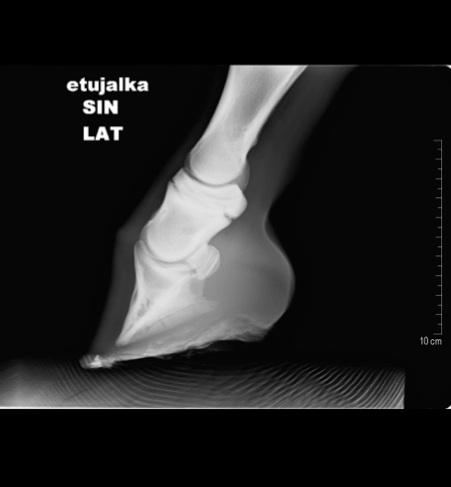

Vuohisnivelen osteokondroosimuutokset ovat yleisiä. Vuohisnivelen etupinnan kappaleet tyypillisesti irtoavat vuohisluun kärjestä. Usein pienikin kappale aiheuttaa ärsytystä nivelelle. Allekirjoittanut suosittelee rutiininomaisesti niiden kirurgista hoitoa nuorella hevosella. Vuohisnivelen takaosan irtokappaleet oireilevat usein vasta erittäin kovassa valmennuksessa. Moni takaosan kappaleista ei aiheuta hevoselle oireita koko lainkaan sen uran aikana.

Takapolven OD- muutokset ovat tavallisia. Useimmissa tapauksissa kirurginen hoito on nuorella hevosella suositeltavaa. Optimitilanteessa röntgentutkimuksessa havaitaan muutos ilman nivelen turvotusta tai ontumaa. Tällöin ennuste on yleensä hyvä. Jos nivel turvottaa, mutta hevonen on ontumaton, on ennuste hyvä tai kohtalaisen hyvä. Jos varsa ontuu jalkaa ja nivel on turvottava, muutos on usein niin laaja-alainen, että ennuste hevosen urheilukäytölle on hyvin varauksellinen.

Muita osteokondroosin esiintymispaikkoja ovat kavionivelen etupinta, kehänivelen etu-/takapinta, kyynär- ja olkanivel. Ennuste määräytyy fragmentin koon, sijainnin ja jo mahdollisen ontumaoireen mukaan.